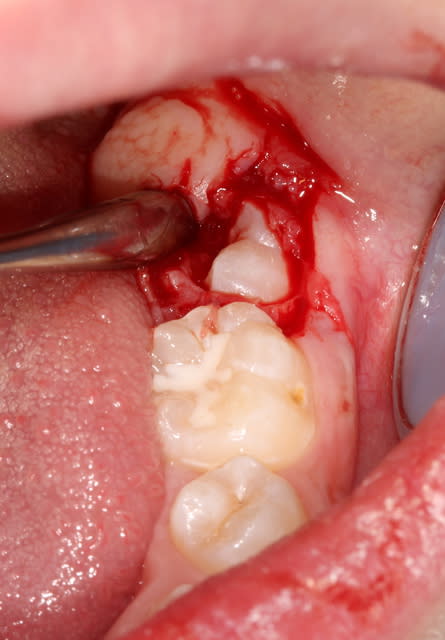

voilà une jeune fille qui n'a rien demandé à personne mais qui a un souci d'évolution des 36 et 46

Vue il y a 3 ans à l'âge de 8 ans, avec un retard d'évolution de 36 et 46 et une agénésie de 25. ( premier OPT). Les parents devaient repartir au pays donc "on verra".

Malheureusement disparue pendant 3 ans, je l'a revoie au mois de juillet à 11 ans donc.

pas d'évolution des 36 et 46 et pas d'évolution non plus des germes de 45 et 35

Il y a quand même eu une édification radiculaire des 6 et une migration, certes elle n'est pas très importante compte tenu de la durée écoulée.

Sur les 2 panos, on voit quand même une bonne épaisseur de gencive. Une gencive fibreuse fait partie des causes de retard d'éruption même si pour les molaires c'est pas le plus fréquent.

En supprimant la cause elles devraient venir se mettre en fonction sur l'arcade.

selon toi il serait donc judicieux de supprimer cette gencive fibreuse au niveau des molaires et cela devrait permettre de voir les 6 sur l'arcade. il y a tout de même une certaine épaisseur de gencive à supprimer!

bonjour l'escaloppe.

Oui, un dégagement chirurgical pourrait solutionner le problème. Au cours de l'intervention, tu peux délicatement luxer la dent pour favoriser son éruption.